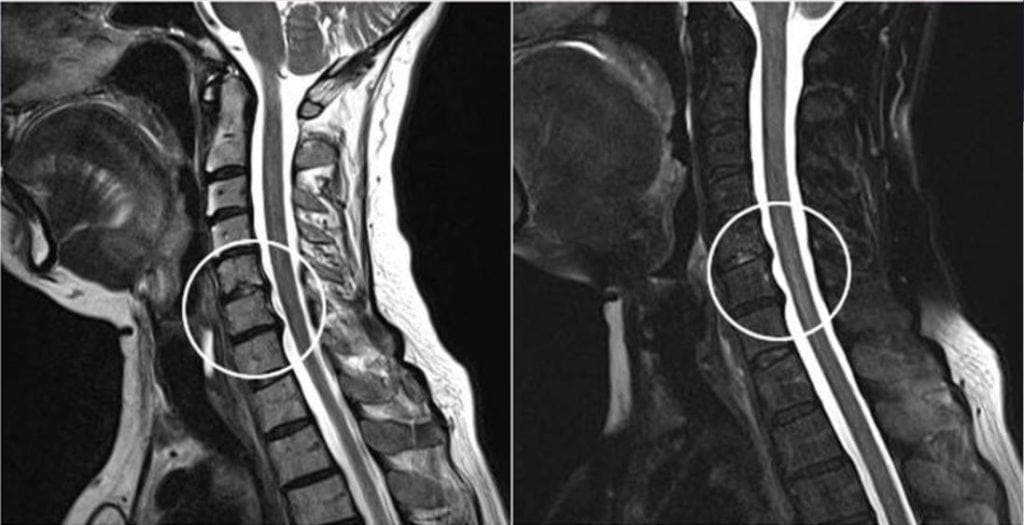

Резкая боль при повороте головы возникает при шейном остеохондрозе 2-3 степени тяжести и часто связана с уже развившимися осложнениями. Сильное повреждение межпозвонковых дисков приводит к нарушению целостности фиброзного кольца и выпячиванию пульпозного ядра за границы позвоночного канала. Формируется межпозвоночная грыжа, сдавливающая не только спинномозговой корешок, но и позвоночную артерию. Этот кровеносный сосуд снабжает кислородом и питательными веществами головной мозг. Поэтому, помимо болей в шее, возникают другие симптомы шейного остеохондроза — головокружения, снижение остроты зрения и слуха, шум в ушах, двоение предметов перед глазами.

Межпозвоночная грыжа — результаты МРТ.

Диагностика

Для выявления деформации костных структур при остеохондрозе, полиостеоартрозе, спондилезе наиболее информативна рентгенография. Деструктивно-дегенеративные изменения хрящевых тканей, в том числе межпозвоночных грыж, а также связочно-сухожильного аппарата обнаруживают с помощью УЗИ, МРТ, КТ.

МРТ шейного отдела.